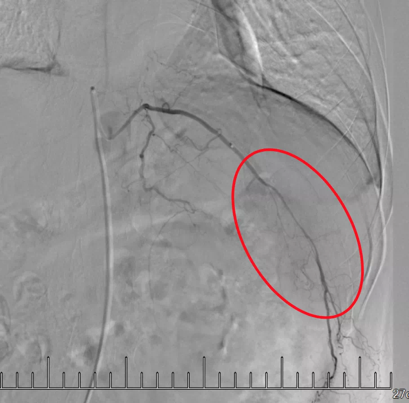

微導(dǎo)管插管到轉(zhuǎn)移瘤所在肋間動(dòng)脈

造影顯示紅圈內(nèi)“烏云”區(qū)域?yàn)槟[瘤。